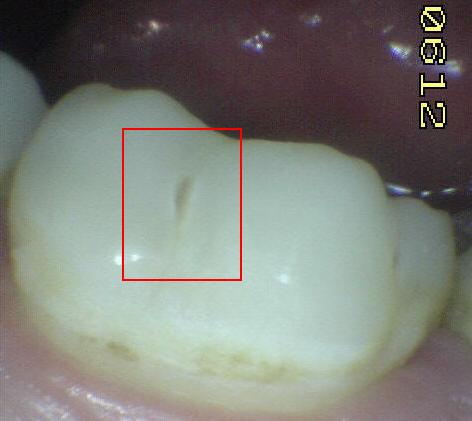

Código 1

(Caries Inicial): Primer cambio

visible en el esmalte seco